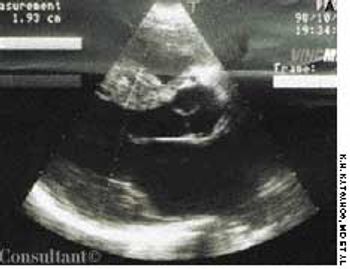

With a 1-year history of episodic wheezing, a 62-year-old woman (a smoker for the past 30 years) was being treated for bronchial asthma, but bronchodilator therapy did not control her symptoms. She was hospitalized with worsening dyspnea and a 4.5-kg (10-lb) weight loss over the past 3 months. There was no hemoptysis.